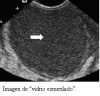

El diagnóstico preoperatorio se hace a través de exploración clínica y ultrasonido trans-vaginal. El ultrasonido trans-vaginal nos muestra un patrón característico de imagen de “vidrio esmerilado”. En ocasiones podemos encontrar un proceso ovárico más complejo en donde se debe hacer diagnóstico diferencial con otras enfermedades del ovario.